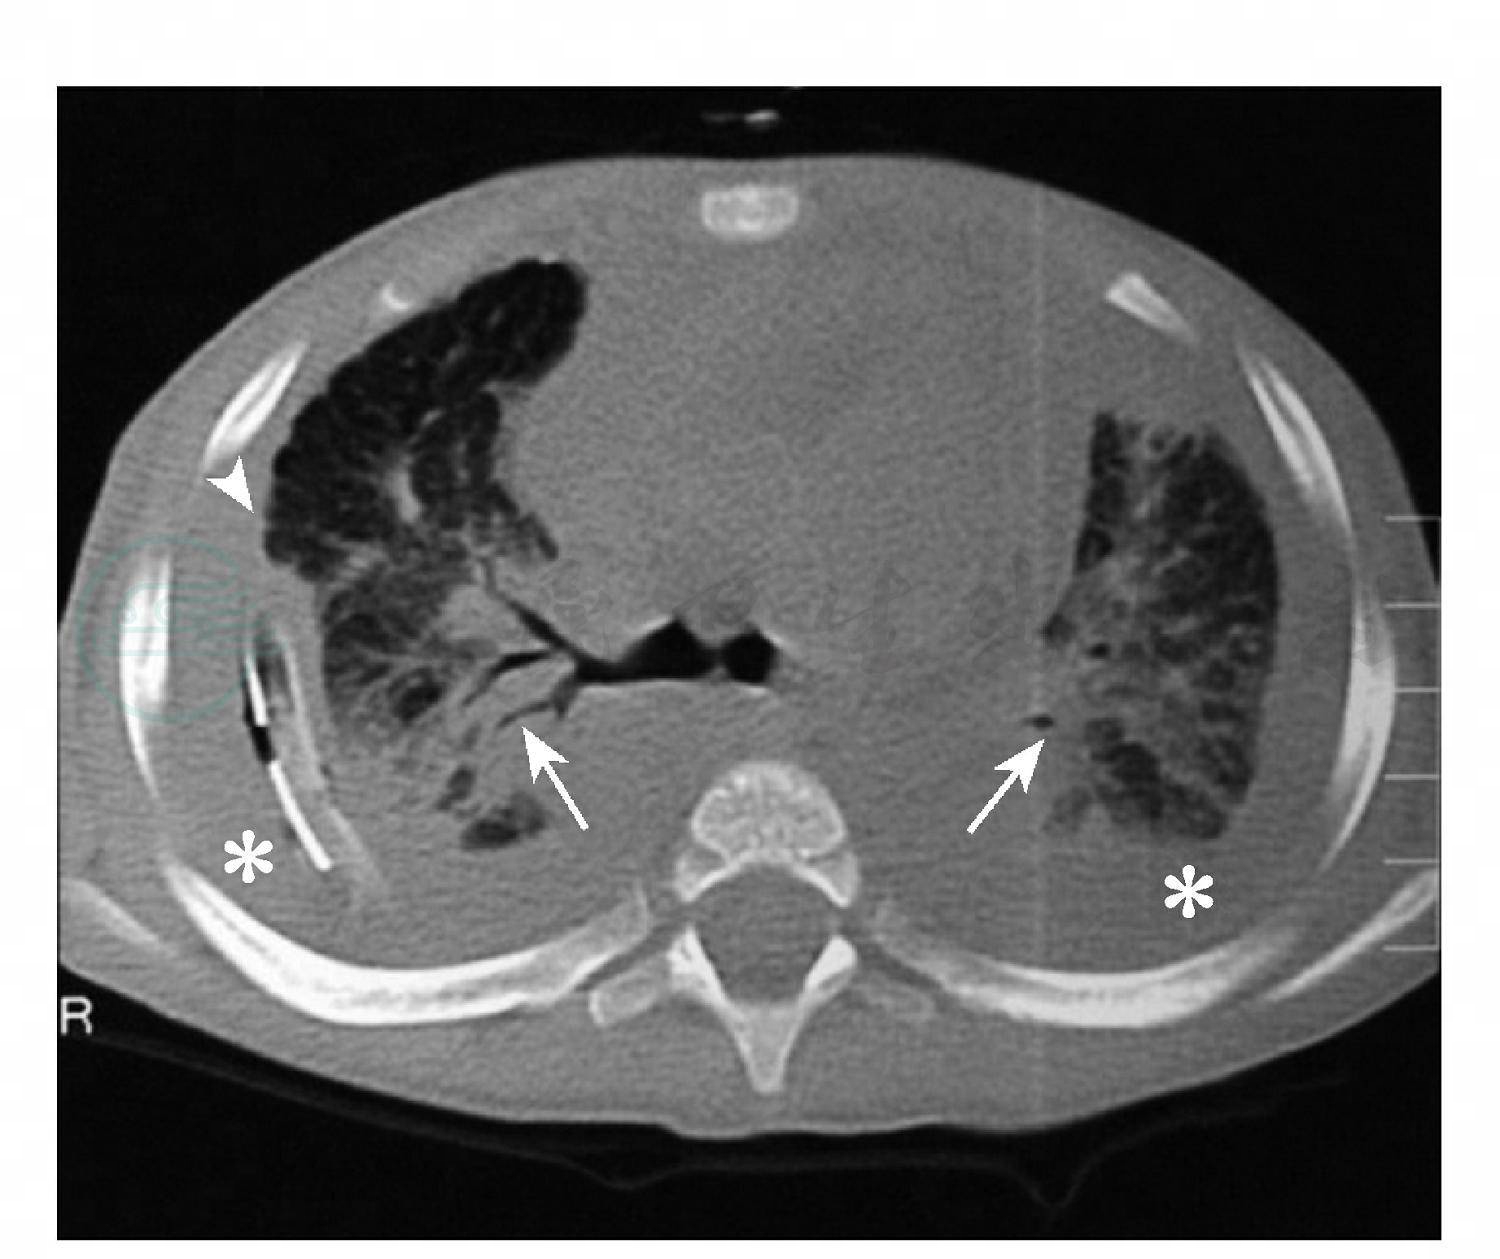

图3肺淋巴管扩张症

女性,17小时,生后6小时出现呼吸困难。CT显示扩张淋巴管层囊状改变